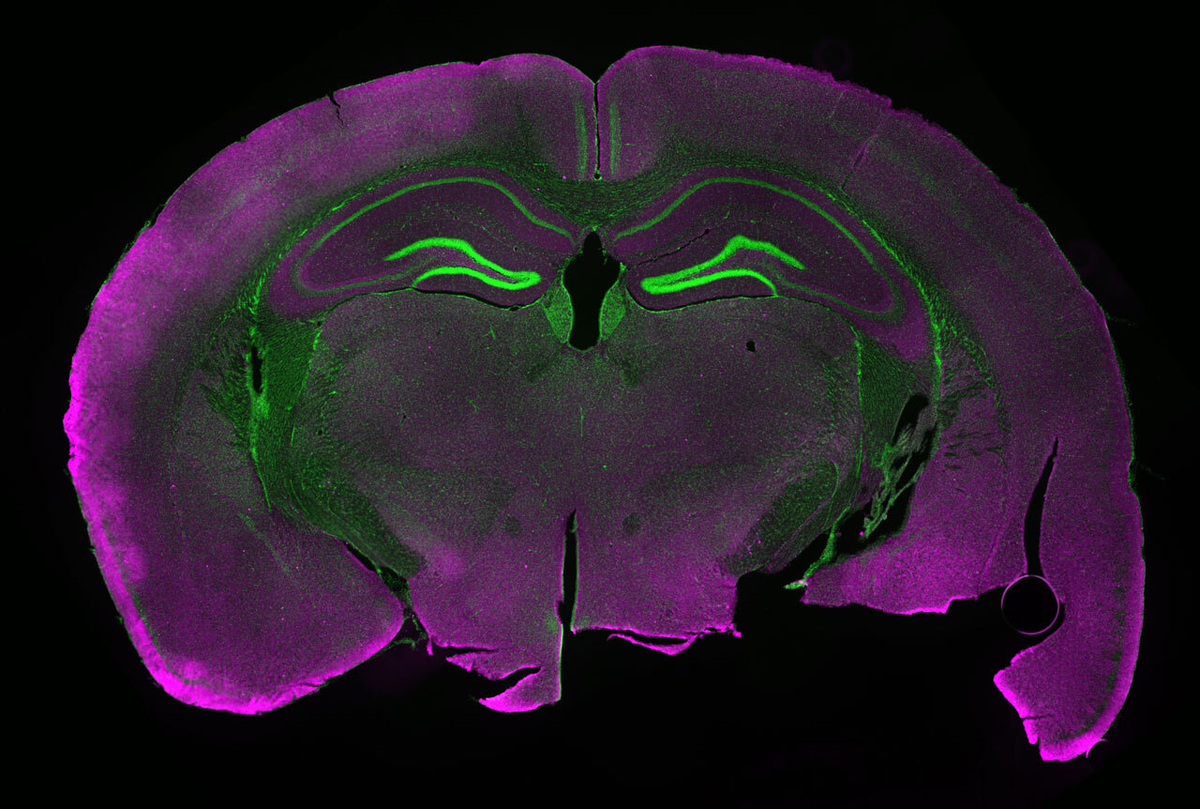

Из миллиардов нейронов головного мозга менее 500 отвечают за подавление чрезмерного употребления алкоголя, выяснило новое исследование, результаты которого напечатаны в журнале Nature Neuroscience.

Применив комбинацию передовых технологий — усовершенствованную волоконную фотометрию, оптогенетику, электрофизиологию и транскриптомику отдельных клеток с применением вирусных векторов, Мартен и его коллеги смогли сузить область мозга, ответственную за подавление пьянства, до конкретного нейронного ансамбля.

На специально выведенных мышах с возможностью визуализации нейронной активности и управления ею Мартен и его коллеги смогли идентифицировать небольшую группу нервных клеток, реагирующих на чрезмерное употребление алкоголя.

Когда нейроны активируются у подопытных животных, вырабатывается флуоресцентный белок, который можно увидеть с помощью волоконной фотометрии. Поскольку это происходит в реальном времени, ученые могут точно определить, какие нейроны активируются при воздействии стимула. Затем, используя оптогенетику (метод безопасной активации клеток светом у живых организмов), эти нейроны можно включать и выключать, словно тумблер. Это позволяет наблюдать изменения в поведении и связывать их с конкретными нейронами.